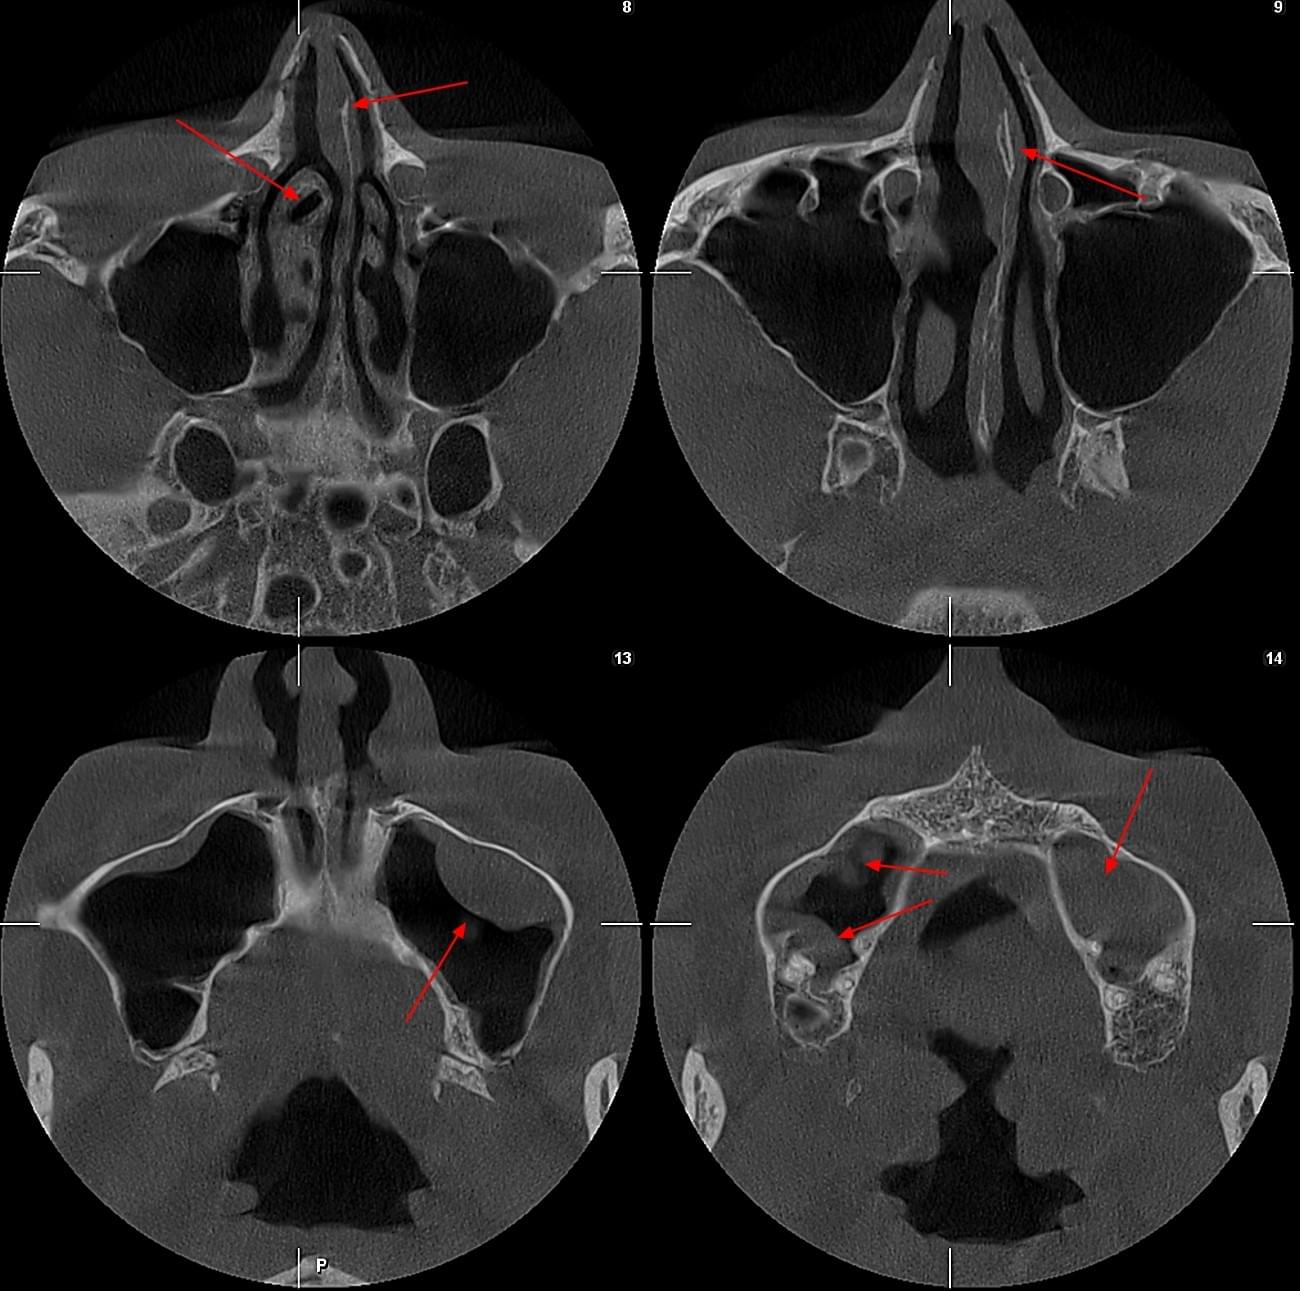

КПКТ (конусно-променева комп’ютерна томографія) — це 3D-знімок високої роздільної здатності. На відміну від звичайного рентгену, КТ показує:

Діагностика гайморових пазух за допомогою КТ

У сучасній медицині КТ придаткових пазух носа (або КТ синусів) — це «золотий стандарт»

діагностики для ЛОР-лікарів та щелепно-лицевих хірургів. Звичайний рентген часто не

показує повну картину, а МРТ не завжди доступний і дорожчий. Комп’ютерна томографія дає

детальну 3D-модель усіх пазух (гайморових, лобних, клиновидних та решітчастого

лабіринту) за 10 секунд і з мінімальною дозою опромінення.